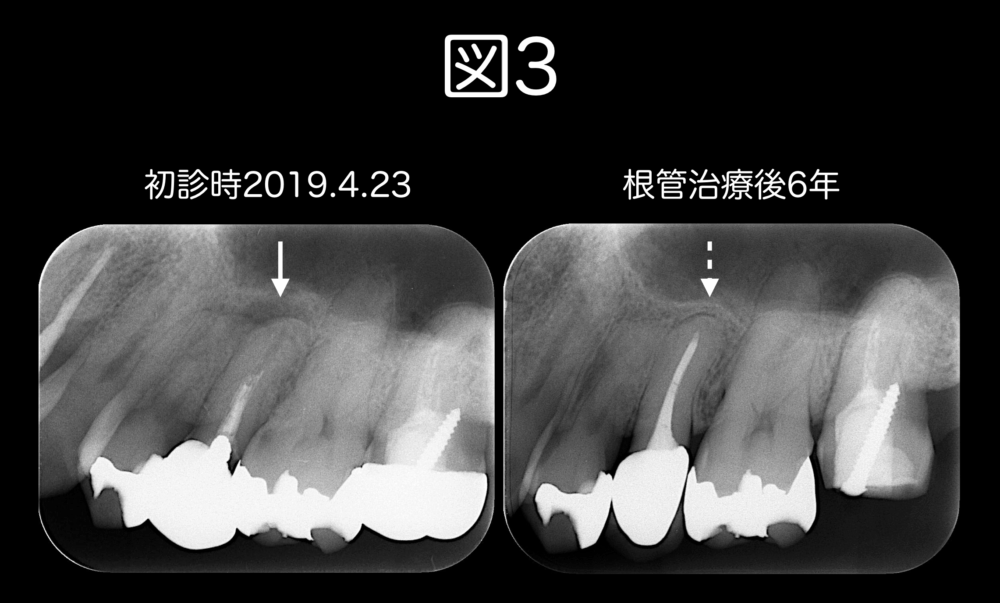

図3は初診時と根管治療後6年のレントゲンです。

虫歯をきれいに取り、無菌的処置を徹底した根管治療を行なって、フィットしたかぶせ物をかぶせると、根管治療後6年の時点で経過良好です。